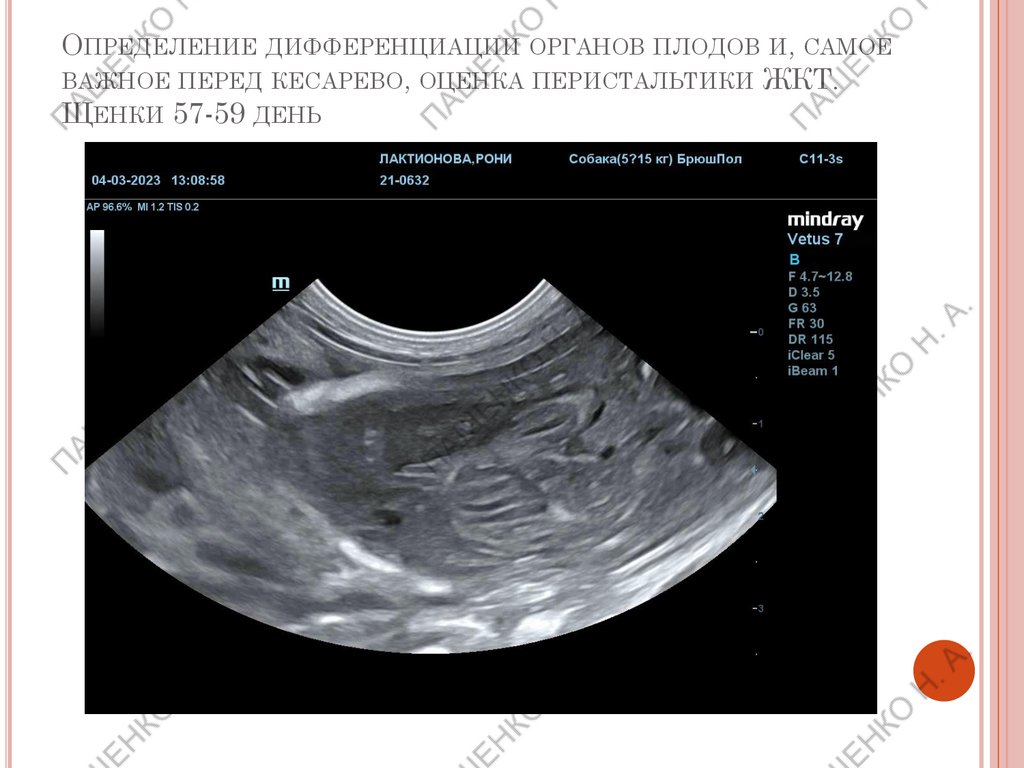

ОПРЕДЕЛЕНИЕ ДИФФЕРЕНЦИАЦИИ ОРГАНОВ ПЛОДОВ И, САМОЕ

ВАЖНОЕ ПЕРЕД КЕСАРЕВО, ОЦЕНКА ПЕРИСТАЛЬТИКИ ЖКТ.

ЩЕНКИ 57-59 ДЕНЬ

Подсчет ЧСС плодов обязателен на поздних

сроках беременности.

ВАЖНО!

При ЧСС выше 180 уд/мин– норма

ЧСС ниже 180 уд/мин– нужен мониторинг.

ЧСС 160-140 уд/мин – кесарево сечение в

течении 2х часов

ЧСС менее 140 уд/мин – необходимо

экстренное кесарево!